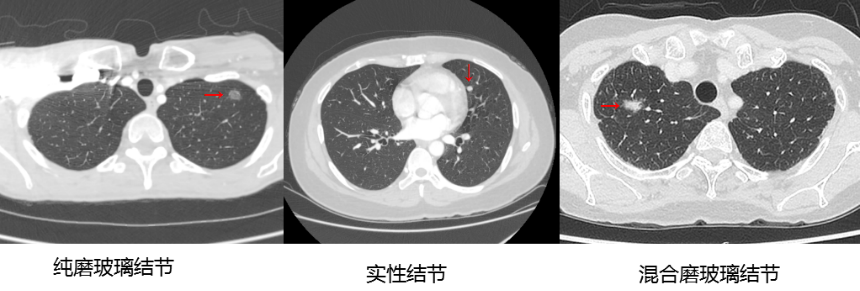

根据CT影像,肺结节可分为以下三种:

●纯磨玻璃结节:像磨砂玻璃一样,呈现出云絮状的阴影;

●实性结节:肺内密度比较高的阴影;

●混合磨玻璃结节:既包含实性成分,也包含磨玻璃成分。